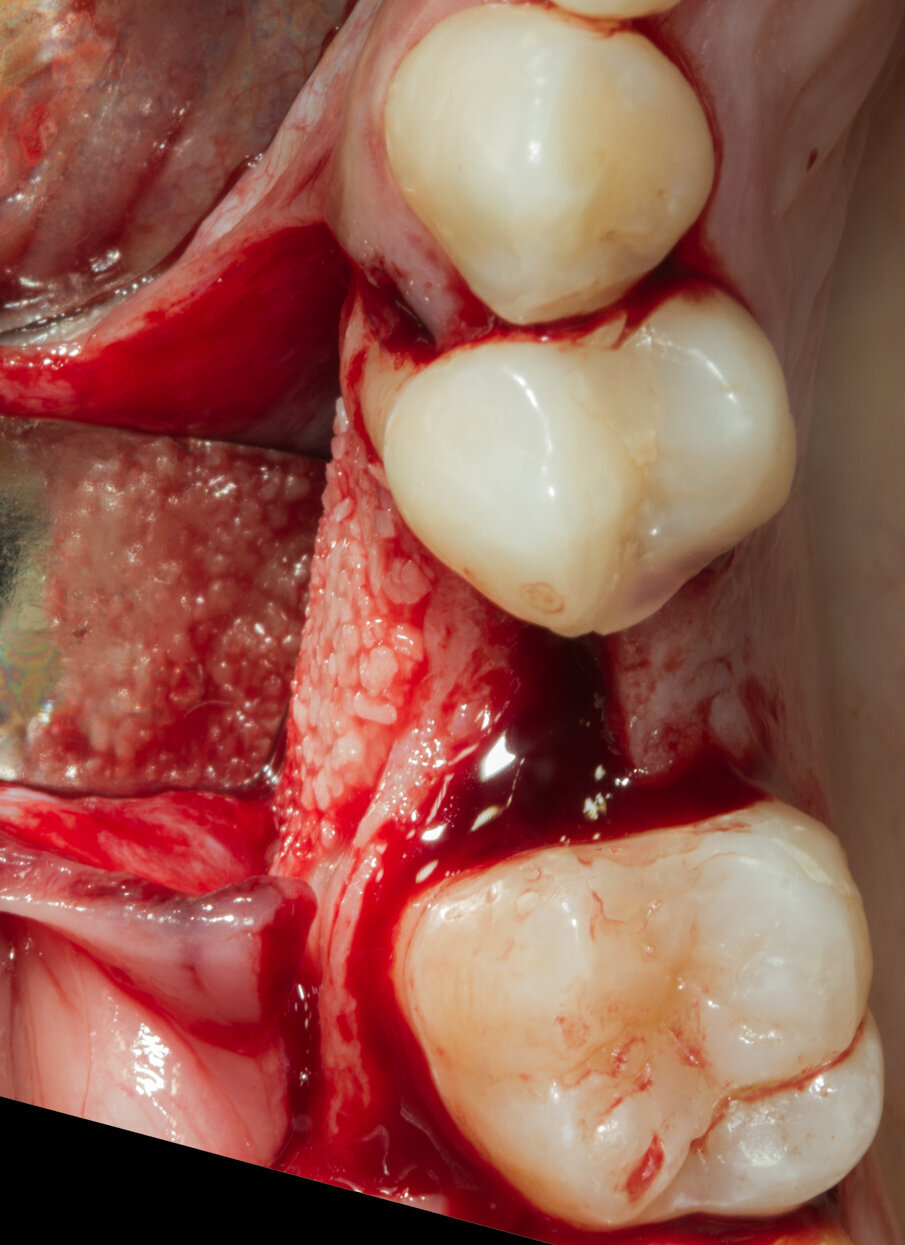

Dopo aver passivizzato il lembo si esegue una sutura a materassaio orizzontale e punto staccato centrale sulla parte crestale e suture semplici sulle incisioni di scarico (Figg. 13, 14). Dopo 10 mesi di guarigione si può procedere all’intervento di posizionamento implantare (Figg. 15-17). Sia dalle fotografie a lembo aperto (Figg. 18, 19) e da quelle di confronto tra la situazione alla baseline e dopo rigenerazione della cresta ossea (Figg. 20, 21) si può valutare come si sia ricostituito un osso ben corticalizzato, vascolarizzato, che ha riempito tutto il difetto osseo preesistente.

Fig. 18 - Ricostruzione completa del Bone Housing.

Fig. 19 - Visione vestibolare.

Fig. 20 - Confronto occlusale tra baseline e sito rigenerato.

Fig. 21 - Confronto vestibolare tra baseline e sito rigenerato.